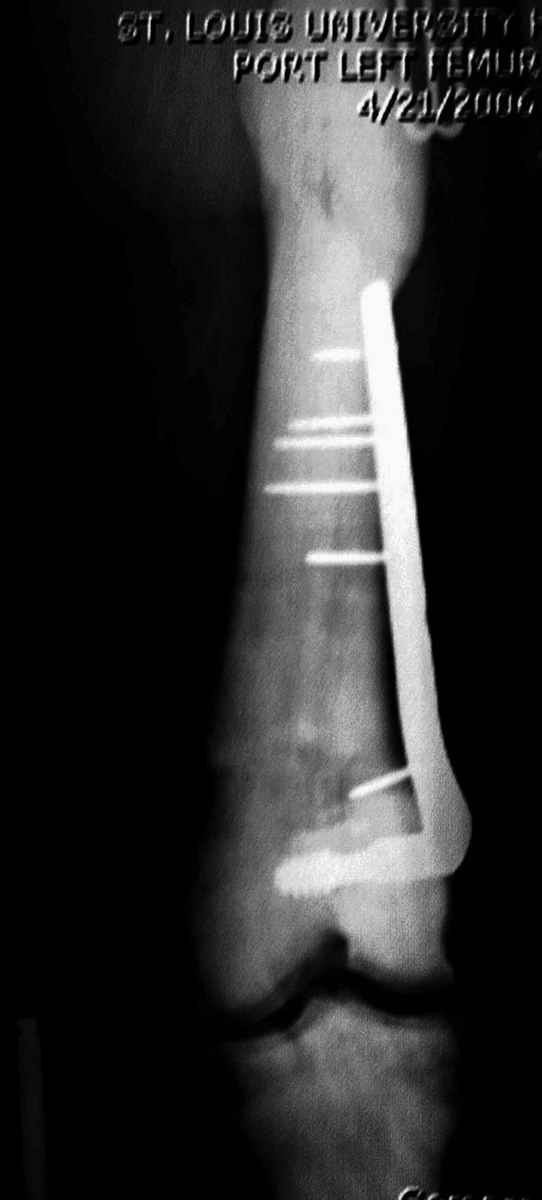

После неудачной попытки скелетного вытяжения в первом мед.учреждении, после осмотра снимков и изучения истории, поставили диагноз “Остеопетроз” или мраморная болезнь, редкая наследственная костная паталогия, где имеется нарушение формации остеокластов.

Конечно, было бы идеальным применение интрамедуллярного остеосинтеза, но учитывая прежний собственный опыт (лечил перелом бедра) и

публикации, предупреждающие о трудностях при обработке кости (иногда из-за неподготовленности инструментария результатом была неадекватная фиксация перелома, или перенос операции из-за фактора усталости оперирующего персонала), решили применить пластину (и в этом же случае был выбран Synthes plate, так что представитель за два дня

зароботал... на десерт тоже).

Заказаны были дополнительные различные дрели, и на следующий день, усиленной бригадой, больного прооперировали, потратив на каждое отверстие около 25-35 минут, хотя сверлили с охлаждением по нарастающей по диаметру сверл и с их заменой каждые 2 мм сверления.

Теперь стоит задача со сращением перелома, из-за отсутствия литературных данных по применению костных стимуляторов при остеопетрозе, и не зная как поведет в этой среде Grafton, все таки надеюсь, что даст толчок к стимуляцию, решил применить пастообразную деминерализованную костную матрицу, расположив спереди между отломками.

Уважаемый Djoldas, огромное спасибо за представленные наблюдения. Пластины во всех 3-х случаях одинаковые, но насколько разным был путь осмысления.

>...учитывая прежний собственный опыт, ....решили применить пластину..., ..потратив на каждое отверстие около 25-35 минут...

Значит операция длилась часа 4? Один раз имел "удовольствие" участвовать в рассверливании канал мраморной кости (все-таки канал узкий, но был, 5-6 мм). Инструмент был новый... Очень тяжело! Но все-таки получилось. Перелом был похожий, гвоздь - Кюнтчера (других тогда не было-1994г), самый тонкий (кажется 8 мм). Снимков к сожалению нет, судьба пациента и его перелома неизвестна :(.